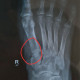

Izin konsul dok pasien post kecelakaan 1 minggu yg lalu, terdapat luka robek pada punggung kaki, sudah di jahit sesaat sesudah kecelakaan (foto klinis tidak ada), pasien inisiatif rontgen sendiri ternyata terdapat fraktur (sesuai foto terlampir) sekiranya apakah fraktur seperti itu perlu dirujuk ke sp ortopedi untuk dilakukan tindakan operasi atau cukup dilakukan balutan imobilisasi saja dok? Terimakasih dokter

Berdasarkan foto rontgen AP: terdapat fraktur avulsi pada proksimal metatarsal pertama di sisi medial, dengan pergeseran minimal.

Apabila ini dikonfirmasi oleh foto rontgen lateral dan kondisi klinis pasien, maka dapat ditangani dengan istirahat, kompres es, elevasi, dan penggunaan gips https://youtu.be/DQjvUWp-mis?si=qp2uFbuxOOQSWWdC atau walking boots.